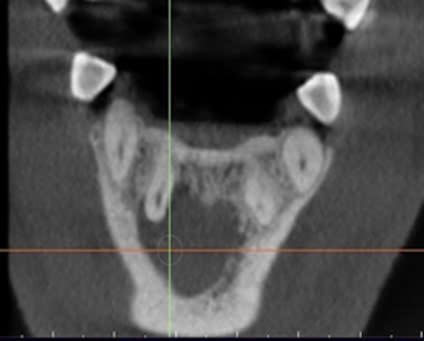

Hình 2. Phim CBCT sau 12 tháng, bệnh nhân Đ.Q.Q

Quá trình lành thương, sửa chữa các mô quanh răng là một quá trình tái tạo phức tạp liên quan đến xương, dây chằng nha chu và xi măng. Các vùng mất khoáng hoà dần dần được lấp đầy bởi xương và cho hình ảnh cản quang nhiều hơn trên xquang. Nếu bản xương vỏ bị phá huỷ, quá trình lành thương sẽ bắt đầu từ việc tái tạo bản xương mặt ngoài và diễn ra hướng tâm, có nghĩa là lành thương từ ngoại vi về trung tâm [10]